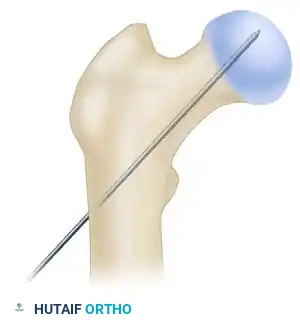

- Place a ball-tip guide pin down the shaft of the femur, advancing it to the level of the physeal scar (or the desired distal extent of the nail).

- Measure the guide pin using the radiographic ruler to determine the appropriate length of the intramedullary nail.

- Insert the nail to a depth that allows for center-center positioning of the lag screw within the femoral head. Once the correct depth is achieved, remove the ball-tipped guide pin.

- Advance a threaded guide pin through the sleeve, up the femoral neck, and into the femoral head. Stop when the pin is within 5 mm of the subchondral bone.

- Confirm appropriate center-center position in the femoral head on both AP and lateral views.